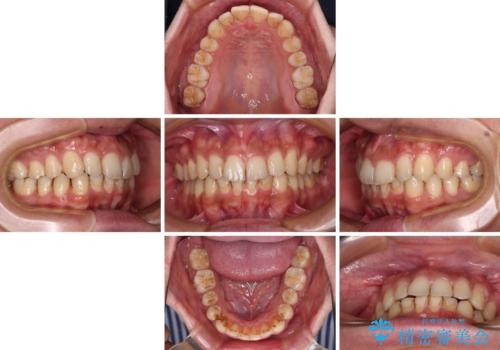

- 上下前歯のデコボコを気にして来院された患者様です。

全体的に叢生は軽度であったため、インビザラインにて矯正治療を行うこととしました。

デコボコの改善はもちろん、下顎前歯が隠れてしまうディープバイトも一緒に改善することができ、奥歯への負担を軽減することができました。